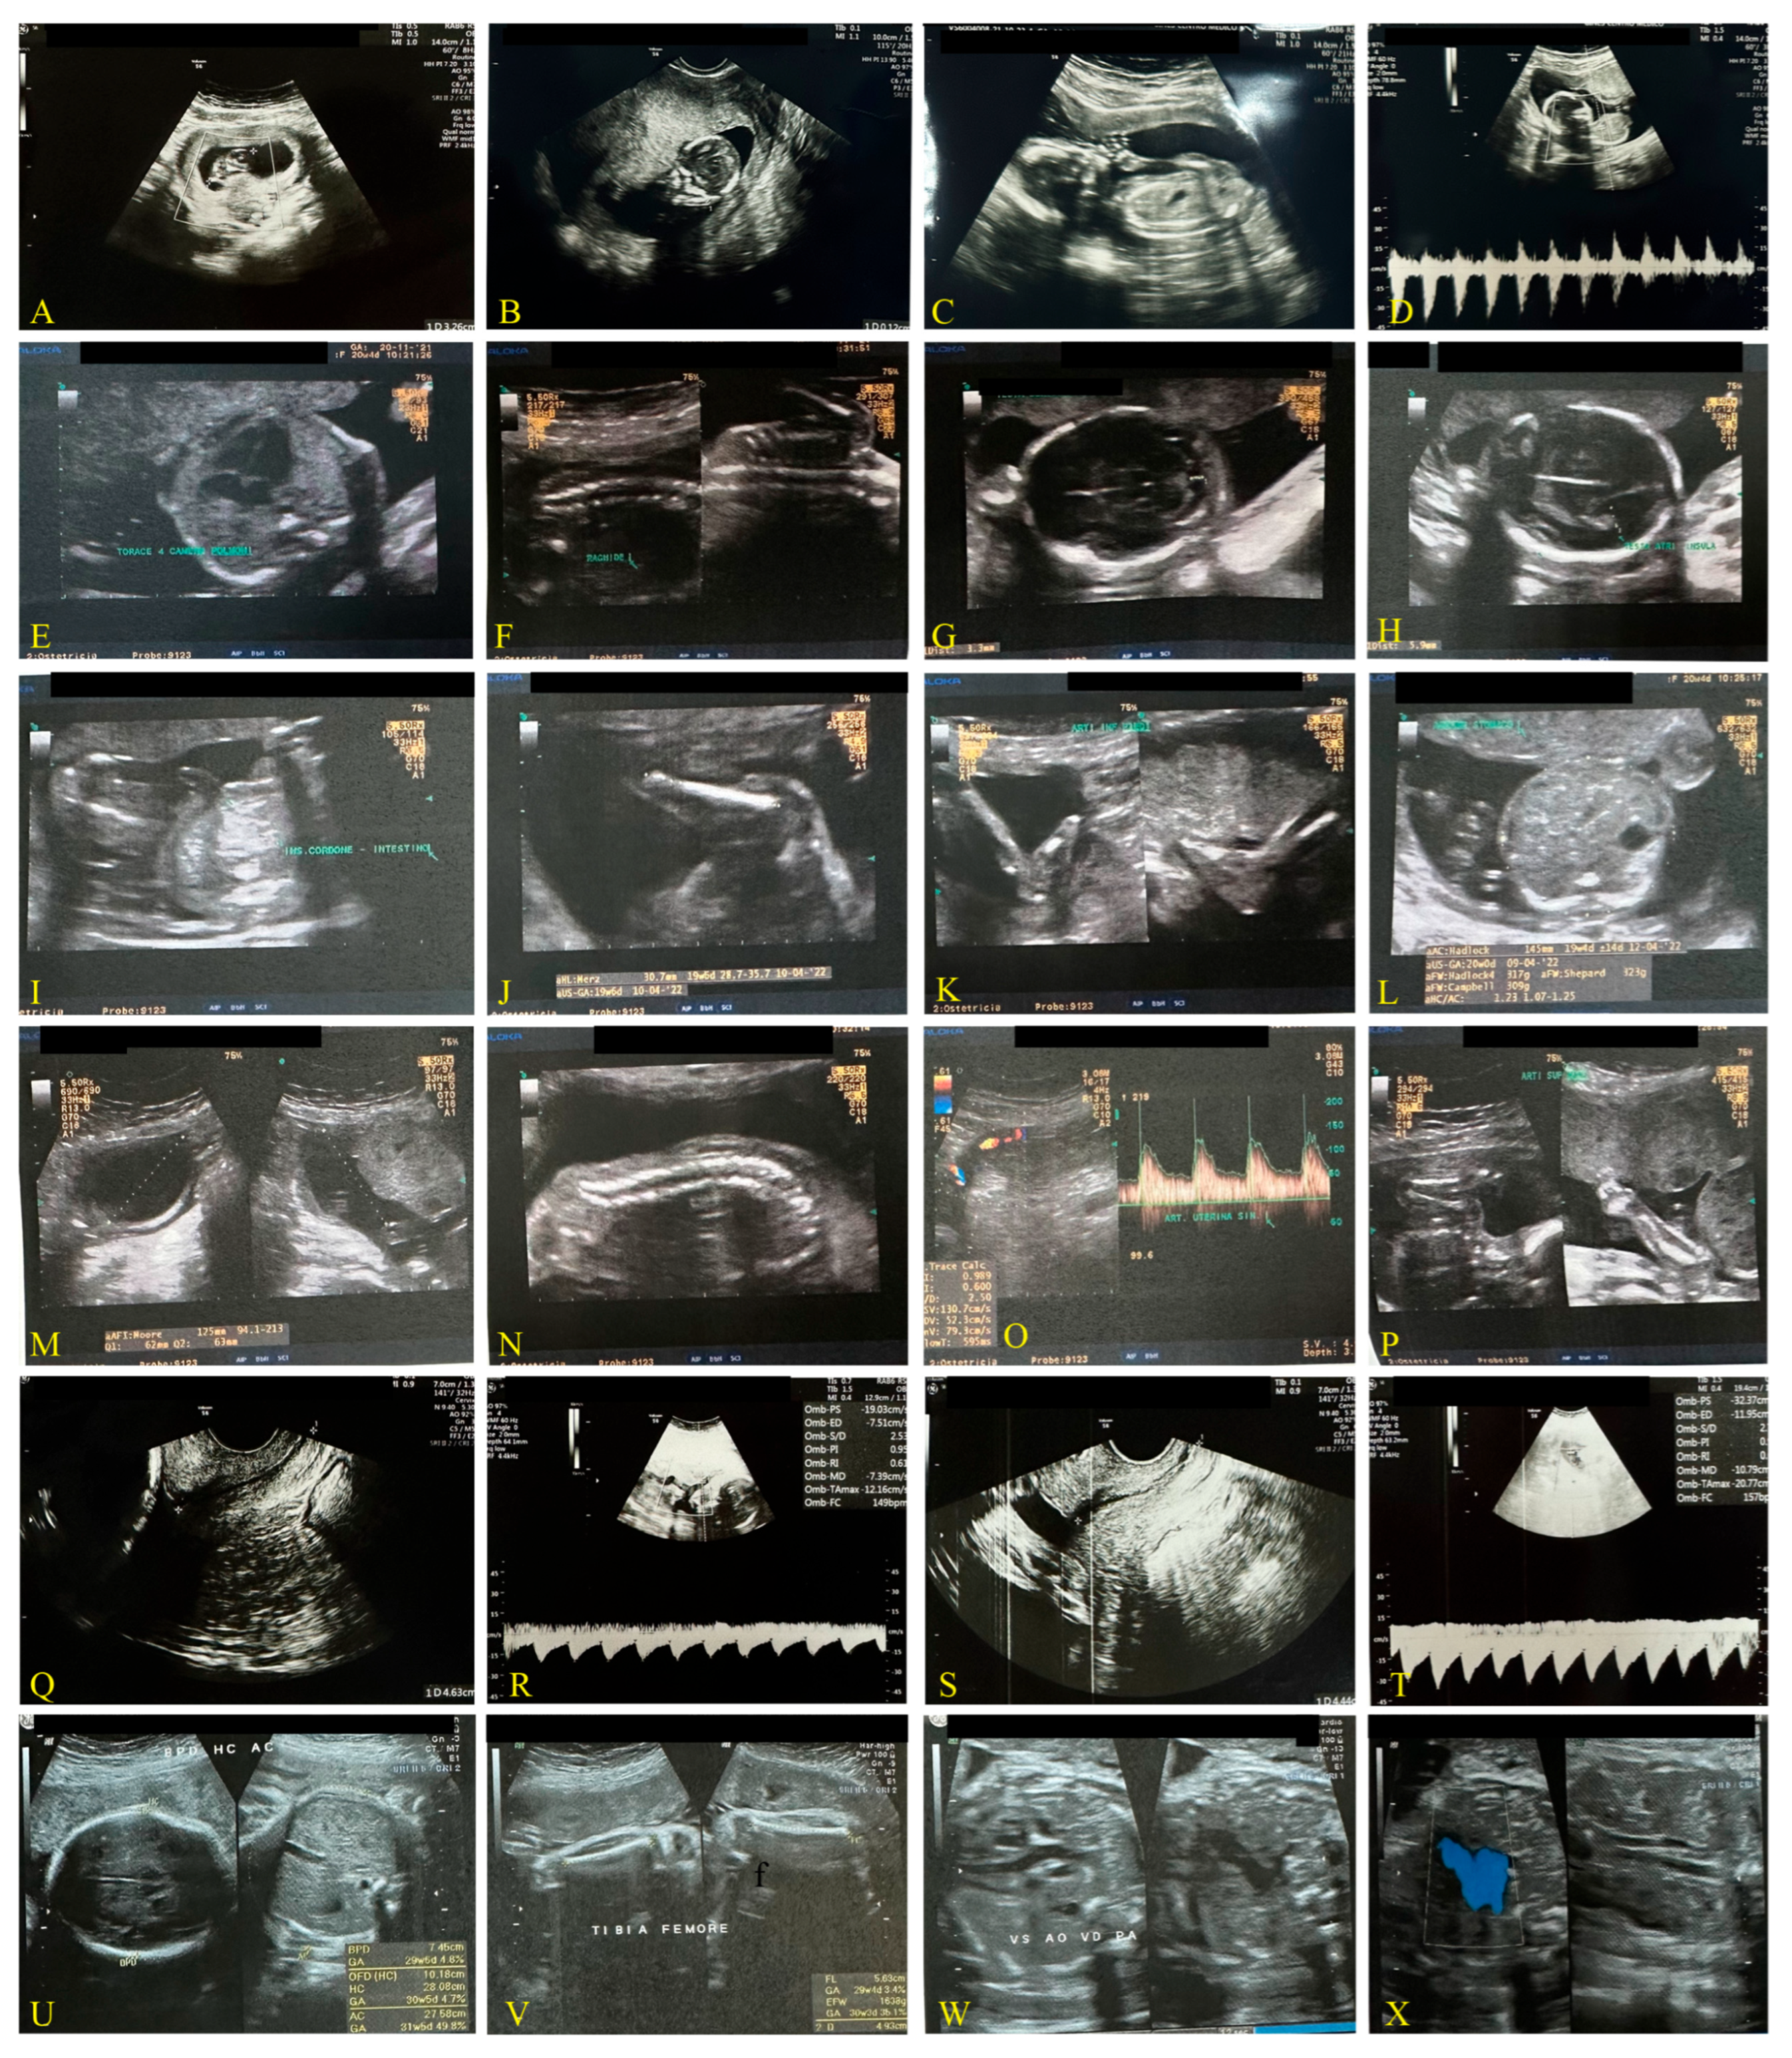

2.1.1. First Case: Pre-Pandemic COVID-19, 2018–2019 (Figure 1)

| Weeks of gestation and Ultrasound data | 20 + 2 days | 21 + 1 days | 20 + 4 days |

| Biparietal diameter (BPD) | 47 mm | 52 mm | 46.4 mm |

| Occipital-frontal diameter (OFD) | 61 mm | 67 mm | - |

| Head circumference (HC) | - | 190 mm | 178 mm |

| Thermal index for bone (TIB) | - | 31 mm | - |

| Fetal corpus callosum (CC) | 172 mm | 190 mm | - |

| Cerebellum transverse diameter | 20.5 mm | 21.5 mm | - |

| Lateral trigon diameter (Lateral Ventriculum) | 6.8 mm | 6 mm | - |

| Abdominal circumference (AC) | 150 mm | 166 mm | 145 mm |

| Femur length (FL) | 32 mm | 36 mm | 32.3 |

| Occiput lateral (head down, facing your side) (OL) | - | 33 mm | - |

| Heart rate | 151 bpm | 140 bpm | 140 bpm |

| Estimated weight | 330 g | 430 g | 320 g |